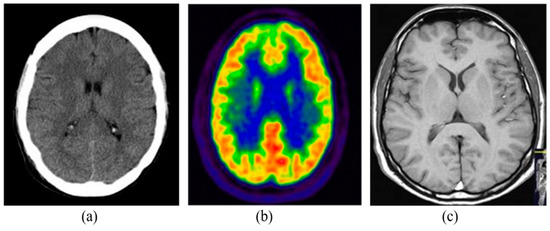

The medical imaging modalities define several methods to capture the image for the structure of some specific organs of the human body. Medical imaging has become an essential part of the clinical procedures due to its effective visualization and quantitative assessment. There are many different modalities of medical imaging available such as Computed Tomography (CT), Positron Emission Tomography (PET) and Magnetic Resonance Imaging (MRI) [6]. Some of the commonly and widely used imaging modalities are detailed in the following subsections. Figure 1 shows the samples of brain images captured from different imaging modalities.

Figure 1. Brain imaging using different modalities: (a) CT, (b) PET, (c) MRI.